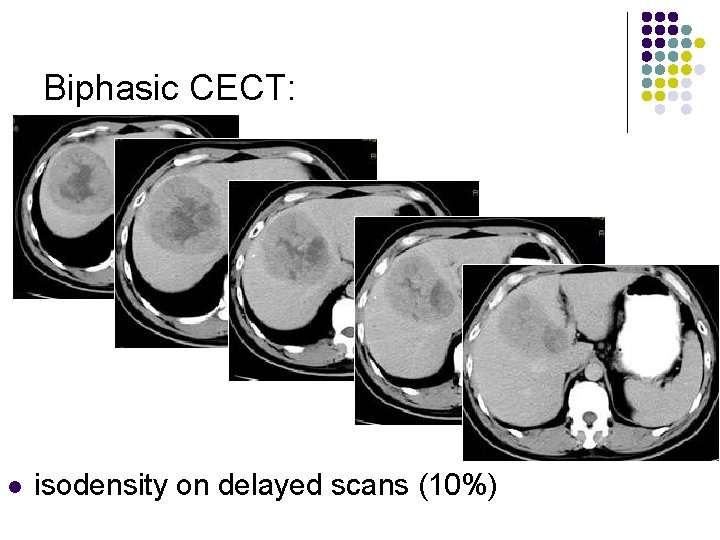

Biphasic CECT: l l l enhancement during hepatic arterial phase (80%) decreased attenuation during portal venous phase with inhomogeneous areas of contrast accumulation isodensity on delayed scans (10%) thin contrast-enhancing capsule (50%) due to rapid washout wedge-shaped areas of decreased attenuation (segmental/lobar perfusion defects due portal vein occlusion by tumor thrombus)

Biphasic CECT: l isodensity on delayed scans (10%)

Biphasic CECT: l isodensity on delayed scans (10%)